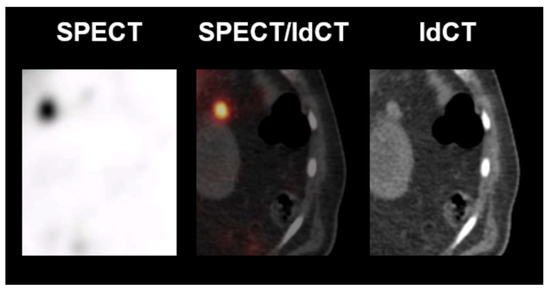

Figure 7 illustrates two challenging cases with visually similar uptake in spleen scintigraphy. In both cases, the use of the newly proposed quantitative cutoff approach would have led to the correct diagnosis and, therefore, would have helped significantly with the unclear visual findings in clinical reading. Figure 7A shows the scan of 60-year-old woman referred for spleen scintigraphy due to an incidental, unclear perisplenic lesion. Using merely visual reading, the lesion would have been prone to be classified as negative, as it has a significantly lower uptake than the nearby orthotopic spleen. Using the cutoff, however, the lesion would have been correctly rated as positive with a ratio of 6.0 (clearly > 0.75). Clinical follow up >18 months showed no evidence of a progression of the perisplenic lesion. Figure 7B shows the scan of a 56-year-old woman with an unclear lesion near the pancreatic tail. Although displaying minimally lower uptake in visual reading as compared to the lesion in Figure 7A, there is still more uptake than in a clearly negative case (e.g., Figure 5) and, therefore, the lesion would have been at risk of being classified as positive in standard clinical reading. Using the newly proposed quantitative cutoff approach, however, the lesion would have been correctly rated as negative (ratio < 0.75). In this case, an endosonography was performed and the histopathological findings were most compatible with a partially sclerosed lymph node.

Figure 7.

Example of two challenging cases in spleen scintigraphy reading. (Left) low dose CT. (Right) 99mTc-labelled denatured red blood cells SPECT. (A) = Rated as spleen tissue using the quantitative cutoff. Clinical follow up showed no evidence of a progression of the perisplenic lesion. (B) = Not rated as spleen tissue using the quantitative cutoff. Endosonographic biopsy was performed and confirmed the rating. Arrows = lesional uptake. Asterisk = pancreas.